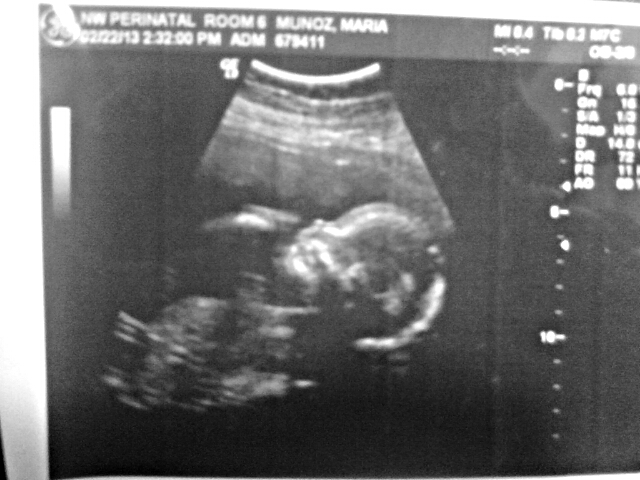

It is a DD!!!

:cheer: Attachment 9255 :cheer: